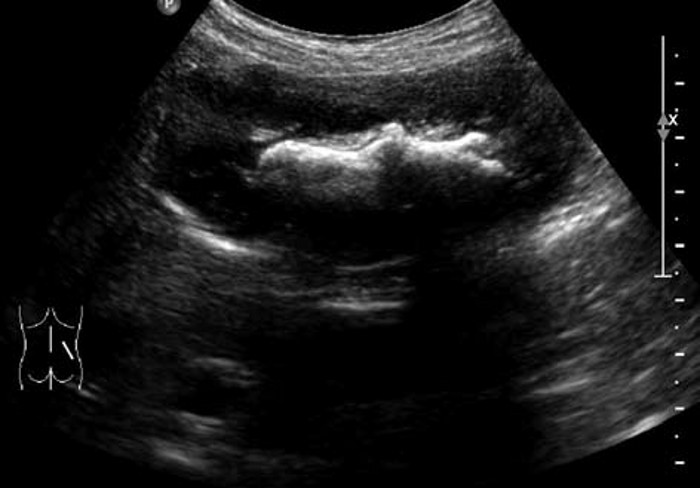

1. 肾内小结石:一般出现在肾乳头旁,表现为圆形或椭圆形的强回声斑点,周围有少量无回声区,后方可有淡声影,有的则不明显。CDFI 显示“闪烁”伪像,有助于小结石的识别。

肾结石的超声图像,肾结石超声诊断及鉴别 2. 中等结石:高强团状回声一般呈新月状,后方声影明显。尿酸、胱氨酸、黄嘌呤结石较疏松,隐约可见光团全貌,后方声影浅淡。